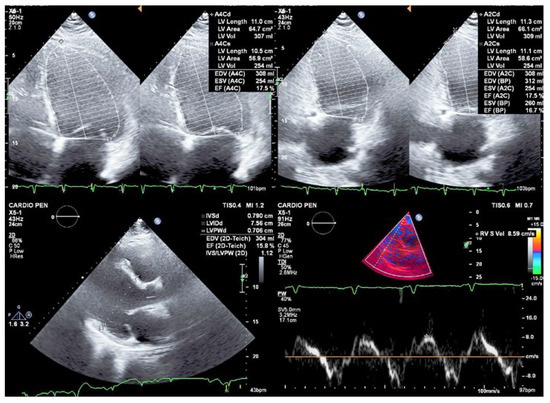

Despite receiving maximum tolerated guideline-directed medical therapy (GDMT) for heart failure (with sacubitril/valsartan 97/103 mg twice a day, bisoprolol 15 mg, spironolactone 50 mg, and dapagliflozin 10 mg), the systolic function did not recover (LVEF of 17%) (Figure 2). Therefore, evaluation for heart transplantation was initiated, although with poor compliance from the patient. Given the increased risk of SCD, an ICD was placed for primary prevention. After approximately one year of follow-up, at the age of 28, the patient received the first appropriate shock for sustained ventricular tachycardia (VT).

Figure 2. Transthoracic echocardiogram showing severe biventricular dilatation and systolic dysfunction (left ventricular ejection fraction of 17%, S’ 8.6 cm/s) due to global hypokinesia.